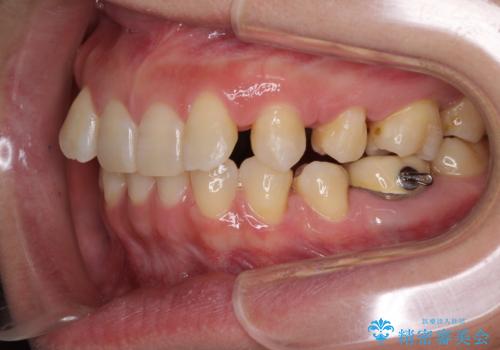

下顎2前歯の欠損 インビザラインによる抜歯矯正

①下顎歯列を拡大し、欠損部に2歯分のインプラント補綴をおこなう

②上顎左右第一小臼歯2本を抜歯、下顎歯列を拡大し、欠損部に1歯分のインプラント補綴をおこなう

③上顎左右第一小臼歯2本を抜歯し、下顎はスペースを閉じる

のいずれかを提案しました。(①から③の順番にお勧めのプランとなります)

いずれもワイヤー矯正が望ましい治療方法ですが、家が遠方であり、近い将来出産される予定もあるとのことで、何とかマウスピース矯正でも対応可能な③にて治療を行うこととしました。

マウスピースでの抜歯矯正特有の抜歯スペースに向かって奥歯が傾斜する動きが顕著に表れ、ディープバイトは改善されませんでした。

前歯のみが強く接触し、奥歯で咬めない期間も続いたため、ワイヤー装置などを補助的に使用し、何とか終了させることができました。